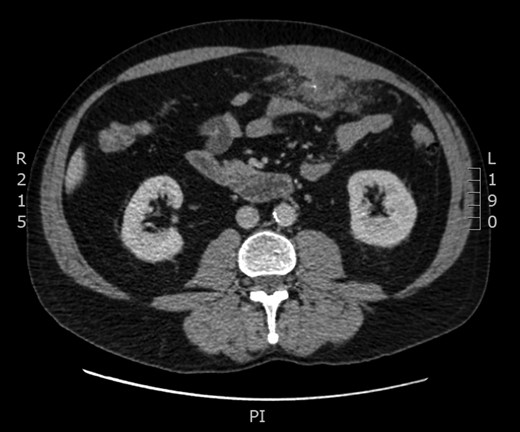

A 61-year-old gentleman presented to the emergency department with 4 day history of worsening left sided abdominal pain, localized to the left upper and predominantly left lower quadrant. This was associated with nausea and subjective fevers. He had no changes to his bowel habits and had no vomiting or urinary symptoms. Physical examination revealed a septic picture with a body temperature of 38.4, HR of 110. He was tender in the Left lower quadrant with localized guarding. Laboratory results showed a white cell count of 10.4 × 109 with neutrophils of 7.90 × 109 and a CRP of 127. A CT of the abdomen showed inflammatory changes present involving the transverse colon located left of the midline, this was associated with a low density peripherally enhancing abscess measuring 2.5 × 3 × 2.4 cm (Figs 1 and 2).

Computated tomography findings with axial image showing inflammatory changes involving the wall of the transverse colon left to the midline with associated abscess. Central opacification consistent with foreign body.